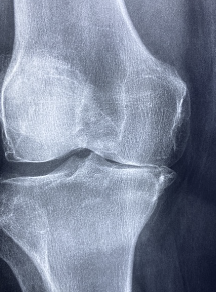

무릎 연골 손상 치료방법

무릎 연골 손상의 치료방법은 손상의 정도와 위치에 따라 달라집니다. 일반적인 치료방법은 다음과 같습니다.

- 보존치료: 연골 손상이 가벼운 경우 보존치료가 가능합니다. 이는 무릎을 안정시키고, 무릎에 부하가 가해지는 것을 최소화하기 위해 일상생활에서 무릎을 지지할 수 있는 고체 지지대를 사용하는 것입니다.

- 약물치료: 진통제나 항염증제를 복용하여 통증과 염증을 완화할 수 있습니다.

- 물리치료: 물리치료는 무릎을 강화하고 유연성을 높여 주는 등의 효과가 있습니다. 전문가와 상의하여 적절한 물리치료를 받는 것이 좋습니다.

- 수술적 치료: 중증한 연골 손상의 경우 수술적 치료가 필요합니다. 수술적 치료 방법으로는 연골 이식, 연골 세포 이식, 연골 유래 줄기세포 이식 등이 있습니다.

- 무릎 수술: 연골 손상이 매우 심한 경우, 무릎 인공 교체 수술이 필요할 수 있습니다.

무릎 연골 손상의 치료는 증상과 원인, 손상의 정도 등 다양한 요인을 고려하여 적절한 방법으로 진행되어야 합니다. 무릎 연골 손상의 경우, 조기에 진단하여 적절한 치료를 받으면 많은 경우 증상이 호전되며, 더 심각한 후유증을 예방할 수 있습니다.